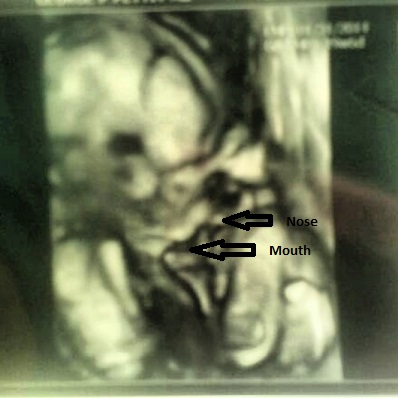

From our 20wk A/S we got 4 pictures. One of which I can tell what it is but can someone tell me what this one is?!

Our tech was so concerned with talking about "worthless people on welfare" that she couldn't be bothered to tell us how much he weighed, his length, or answer any questions about what was what. I think I see a face here....but it's the face of a opossum with one giant thumb. ![]()

I had to make this for my husband after ready what ClrkKntismyAE had to say because he was just as lost as I was...get ready to chuckle lol.

I'm assuming I'm correct now.

To me, it looks like he's squished up really small, at a profile angle. Those limbs look like legs?